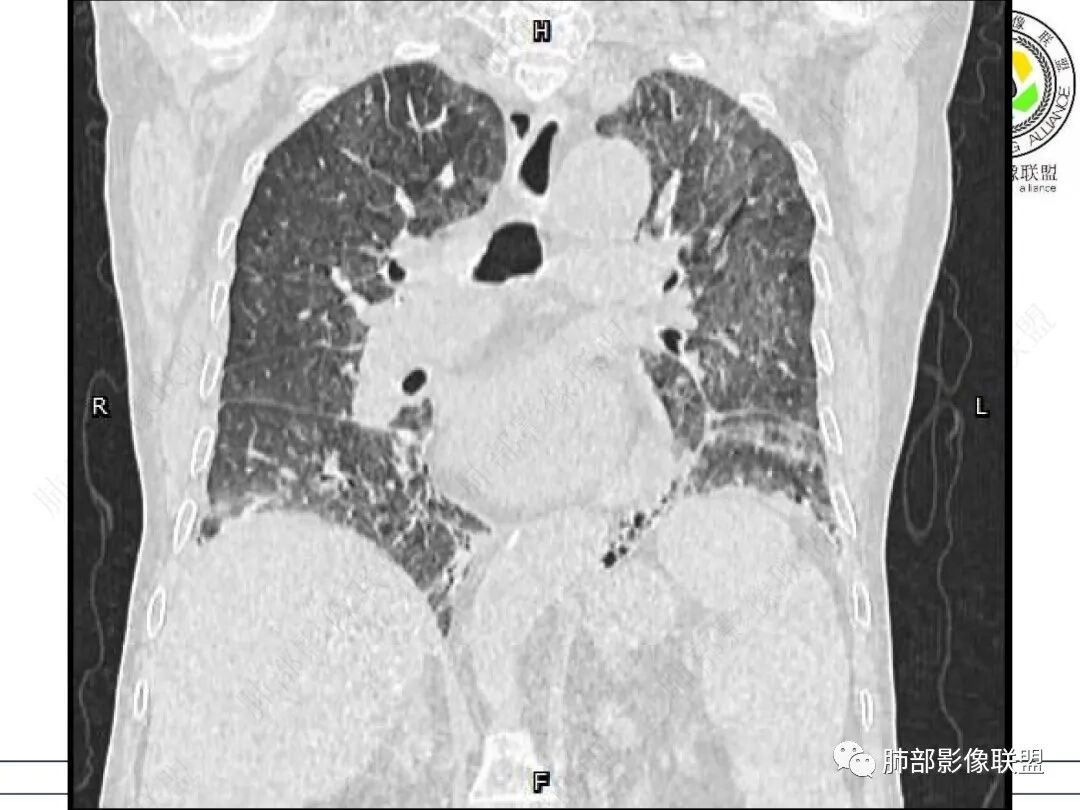

心脏大,胸腔积液,小叶间隔增厚,双肺磨玻璃影,考虑存在肺水肿,另双肺间质性炎性,类风关病史,考虑CTD-ILD,左肺上叶结核可能。

两肺叶后肋膈角区见多发蜂窝状结构破坏表现,双肺叶小叶间隔增厚,左肺上叶后段及舌段和右肺中叶胸膜炎性肉芽肿特点,双侧胸腔少量积液,有类风湿性关节炎治疗史,结缔组织相关性间质性肺病。

老年女性,类风湿关节炎病史多年。发热。以两肺下叶为主弥漫磨玻璃及网格状透亮影,透亮度减低,局部小蜂窝状改变;两肺胸膜下散在几枚实性病灶;双侧胸腔积液。考虑RA-ILDNSIP

两下肺多发蜂窝状表现,双肺小叶间隔增厚,双肺磨玻璃影及部分炎性肉芽肿表现,双侧胸腔积液,有类风湿性关节炎治疗史,结缔组织相关性间质性肺病。患者C反应蛋白和降钙素原都高,是否合并细菌感染

女,71,外阴疼痛2周,发热1周。类风关、高血压、高血糖、卵巢囊肿、肠粘连、胆囊结石等病史及相关药物治疗史。胸部CT:两肺弥漫磨玻璃,血管束增粗,两下肺后肋膈角多发蜂窝,对称分布,双侧胸腔少量积液,纵隔窗心脏大血管影明显增宽。考虑混合性病变,CTD-ILD,并肺水肿?并PJP?。

①影像表现复杂:较弥漫间质性改变,对称磨玻璃密度为主,小叶间隔增厚,有一定重力分布趋势,未见明显纤维化,气囊及蜂窝位于肺边缘,未见典型“月弓征”。心脏影增大,双侧胸腔积液。